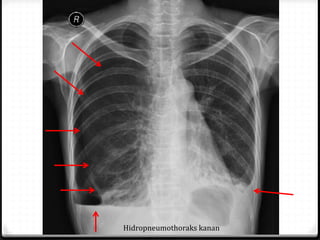

Hidropneumothoraks kanan

Pneumothoraks

0 Udara pada rongga pleura

0 15%–40% ditemukan pada trauma thoraks

0 Ruptur alveoli karena ada tekanan meninggi secara tiba-tiba

pada intrathorakal akibat trauma dengan atau tanpa fraktur

costae

0 Radigrafi polos >>

0 ± 10% tidak dapat dievaluasi dengan radiografi polos  CT scan